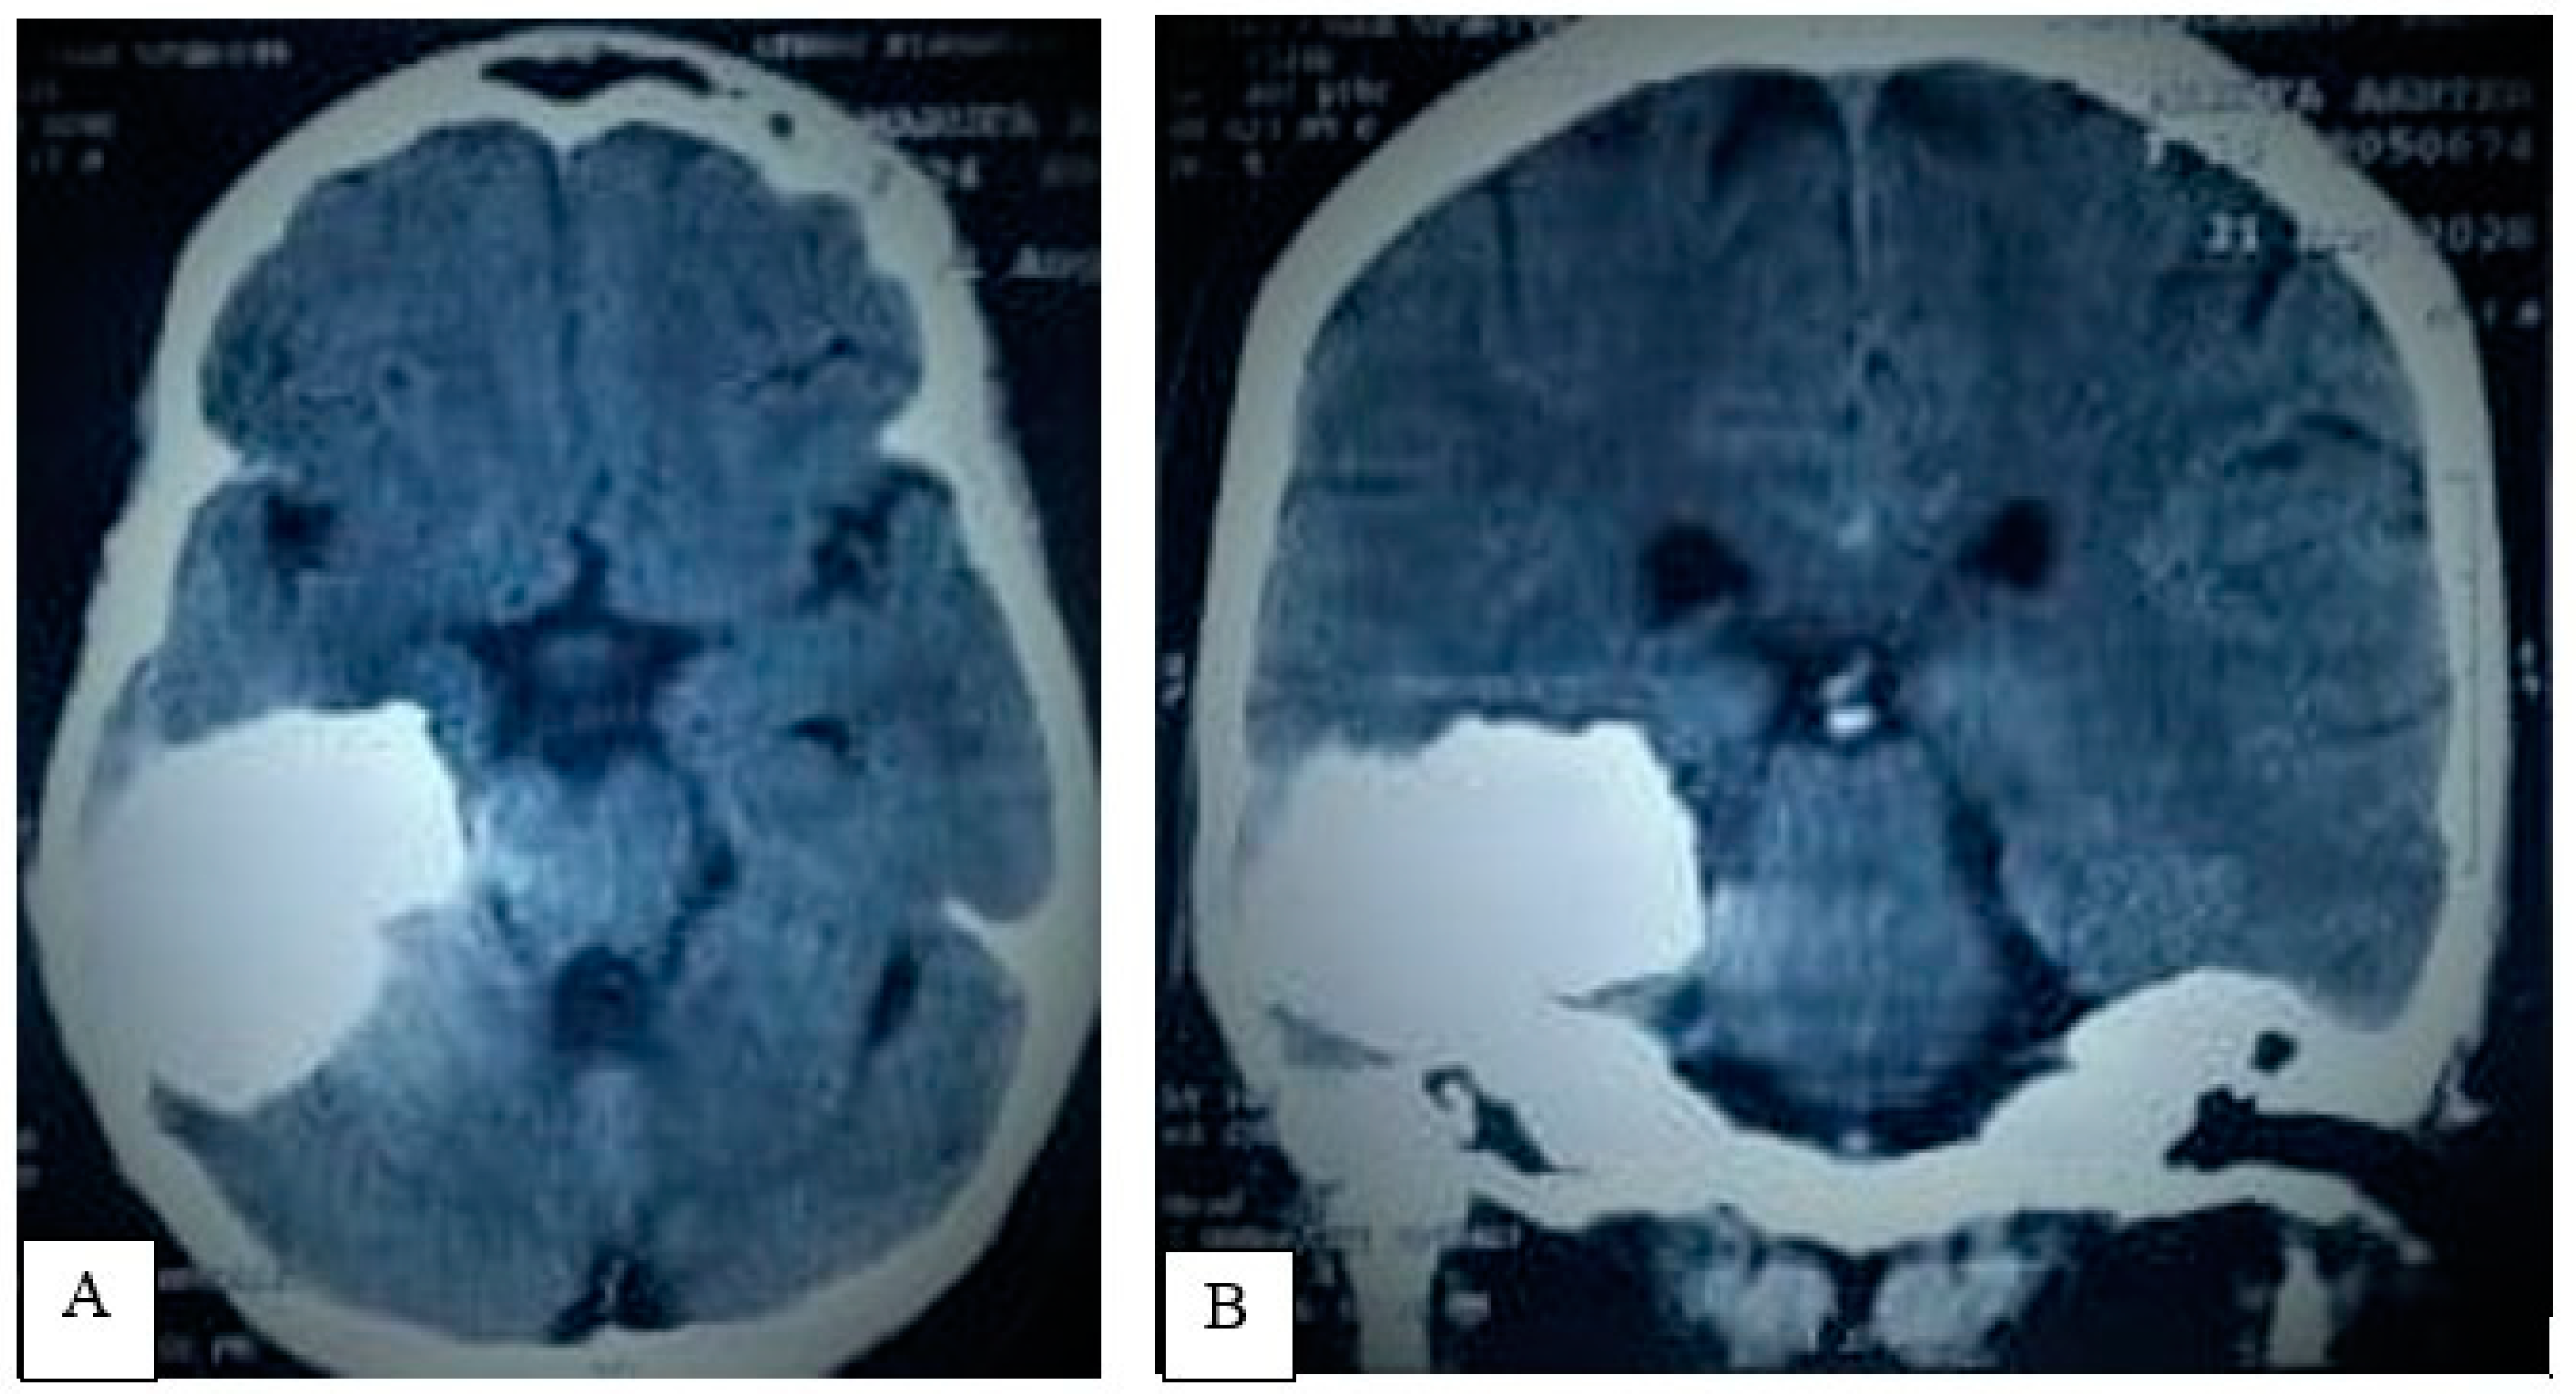

3.1.2. Preoperative Imaging

| 32 | Present case | 2021 | 25 | F | R | Headache, seizure, visual disturbances | Solid calcified mass | GTR | No recurrence at 6 months |